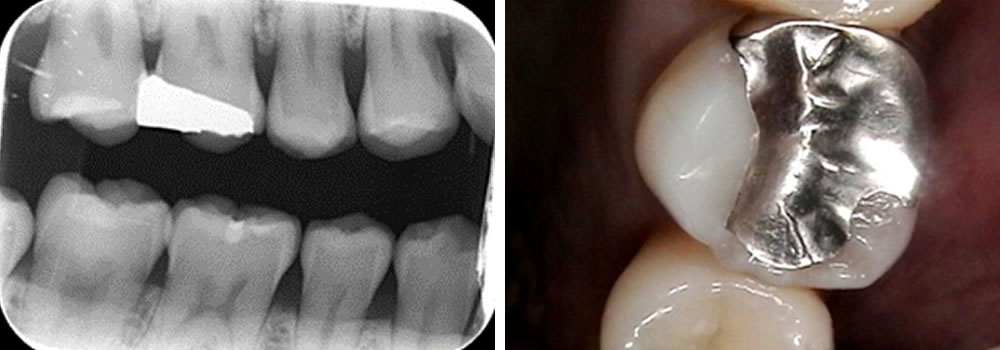

再発した銀歯の虫歯治療後にセラミックで修復した症例

再発した銀歯の虫歯治療後にセラミックで修復した症例 メンテナンスの際、レントゲンを撮影し、左下6番目の歯の銀のつめ物の下で虫歯になっていることが分かりました。 患者さまに説明し、治療をすることとなりました。 銀歯の除去・ […]